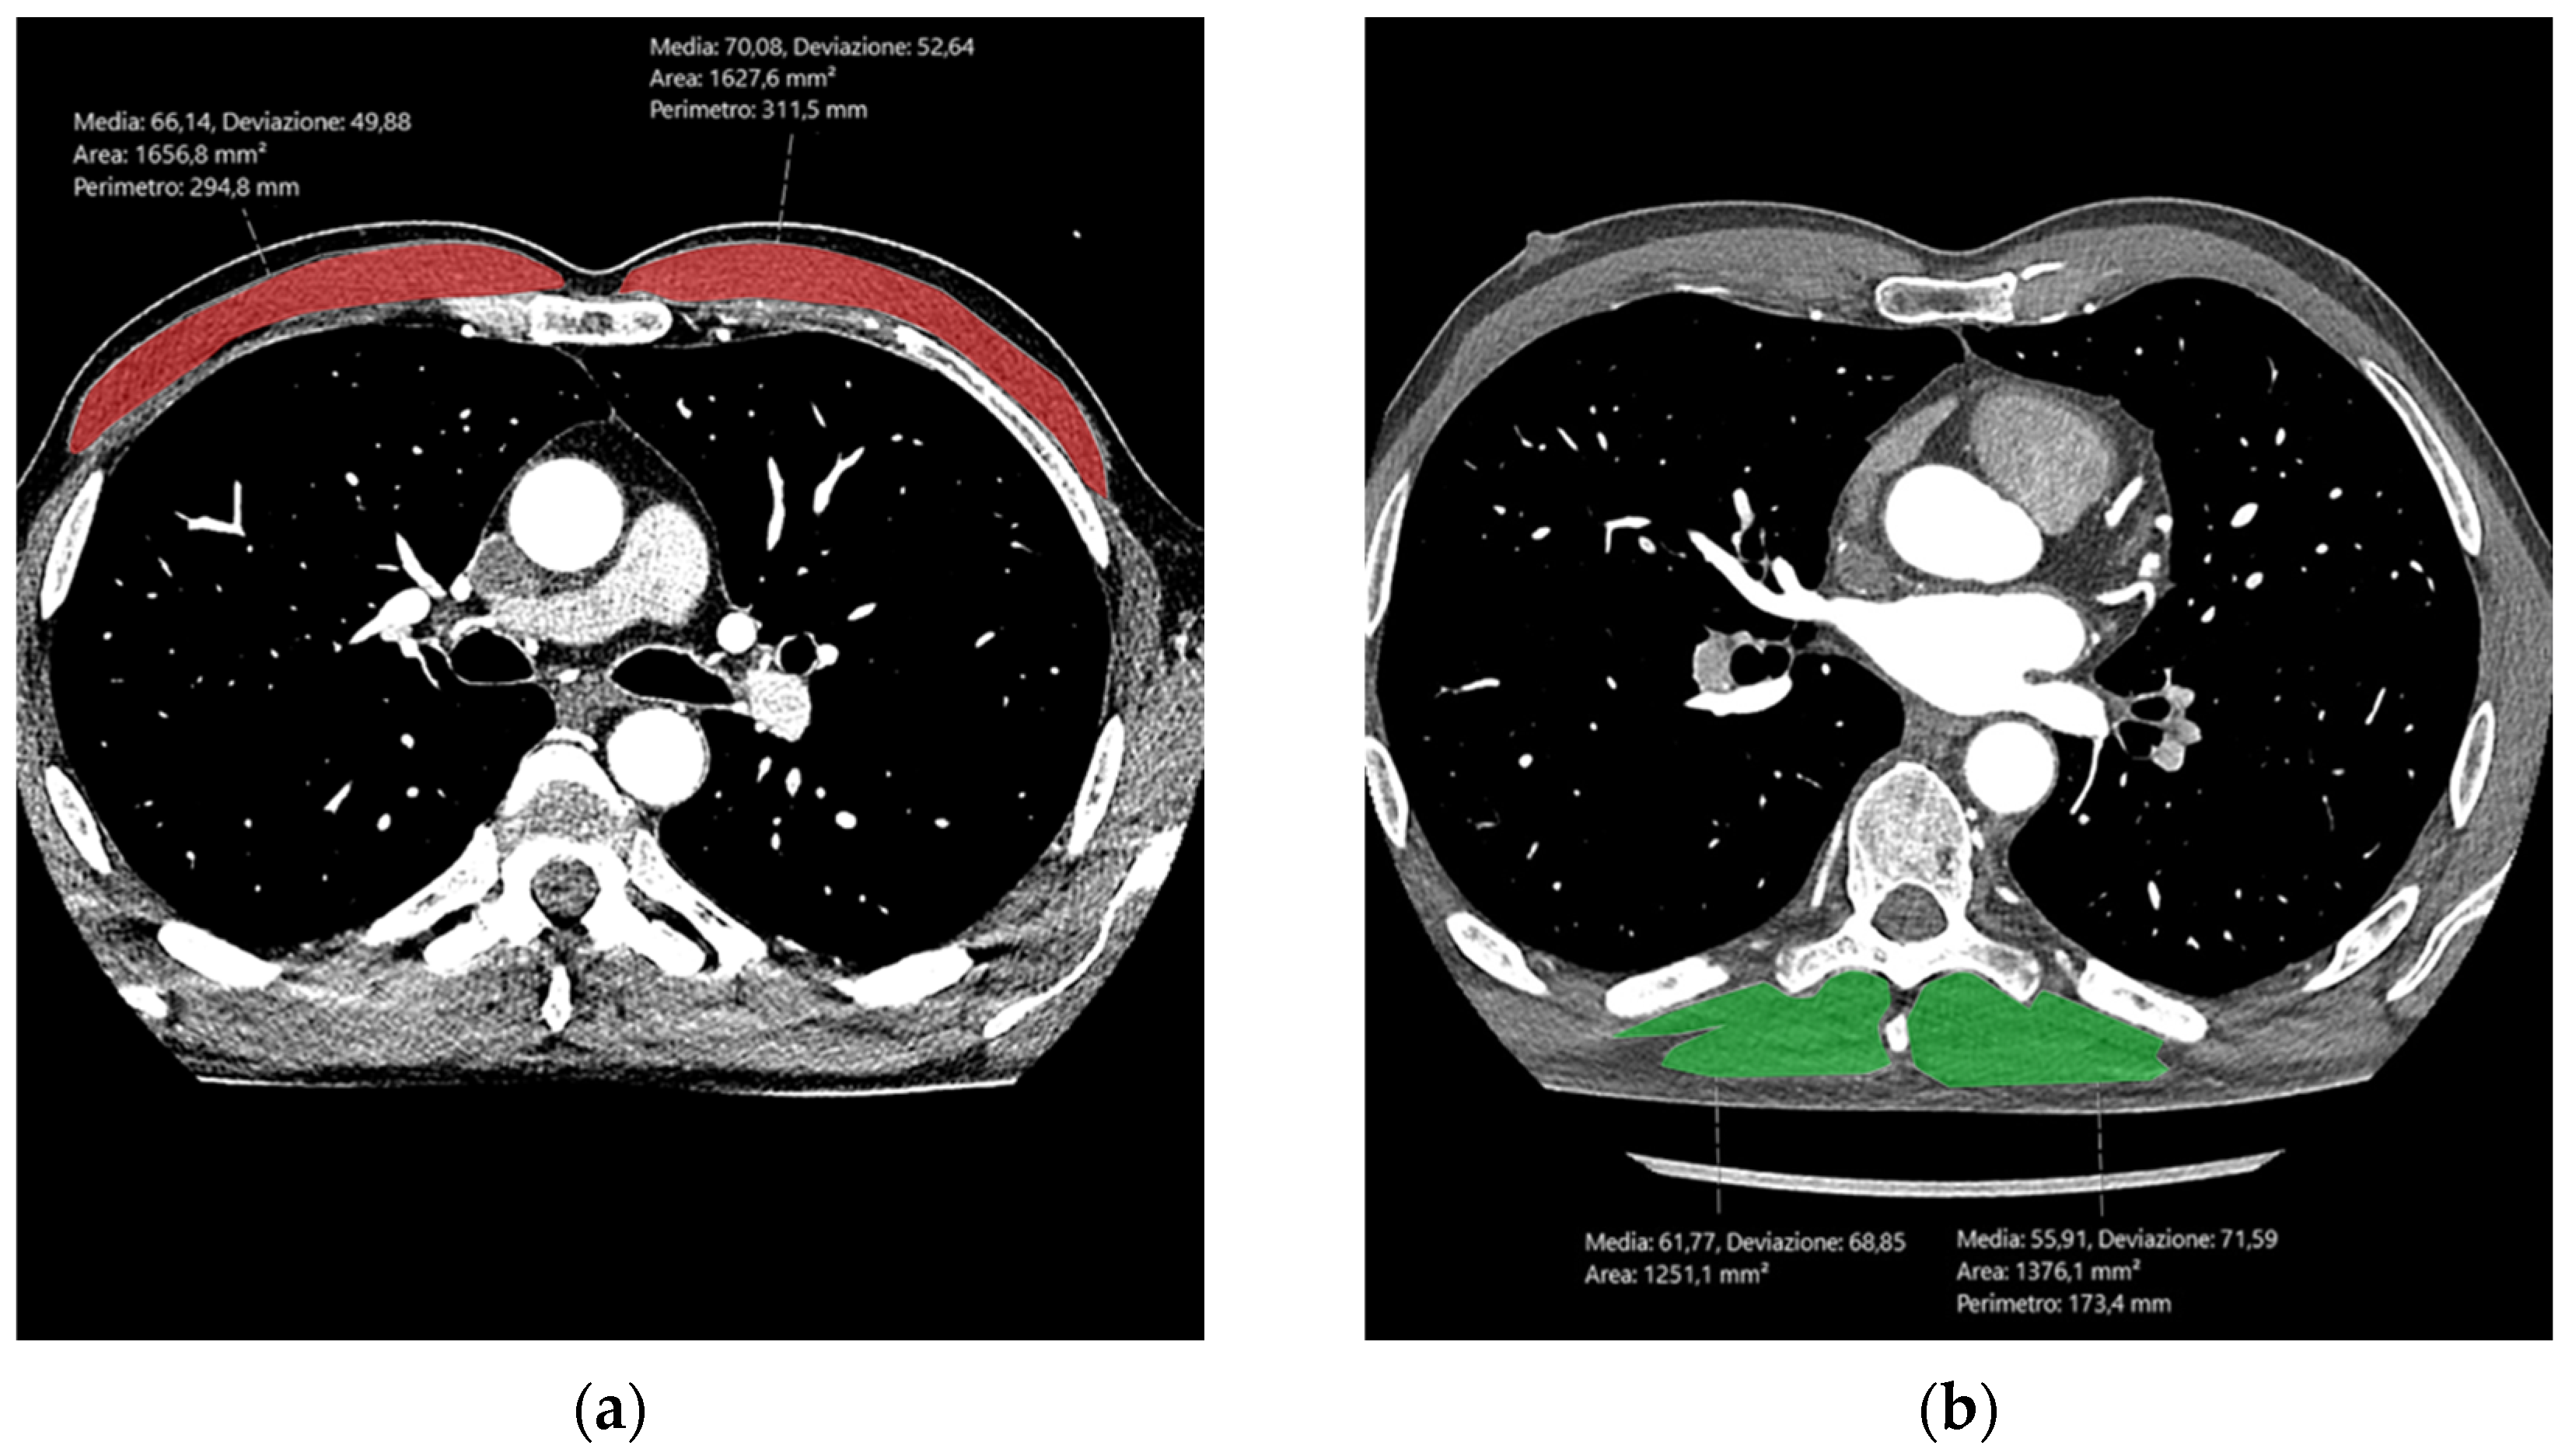

2.3. CCTA Image Evaluation